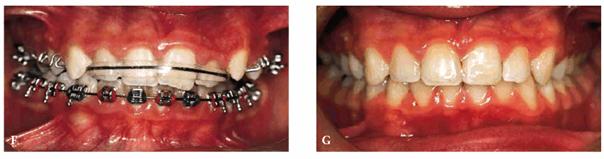

From an orthodontic perspective, a serious skeletal Class II with deep bite is becoming more and more evident. Therefore, orthodontic treatment has been initiated in both arches to align the dentition over the basal bone in harmony with the surrounding hard and soft tissues, as well as to achieve good esthetics (Figures 27-7F and G

Figure 27-7F and G: The same patient during the orthodontic treatment and after. Good esthetics has been achieved.